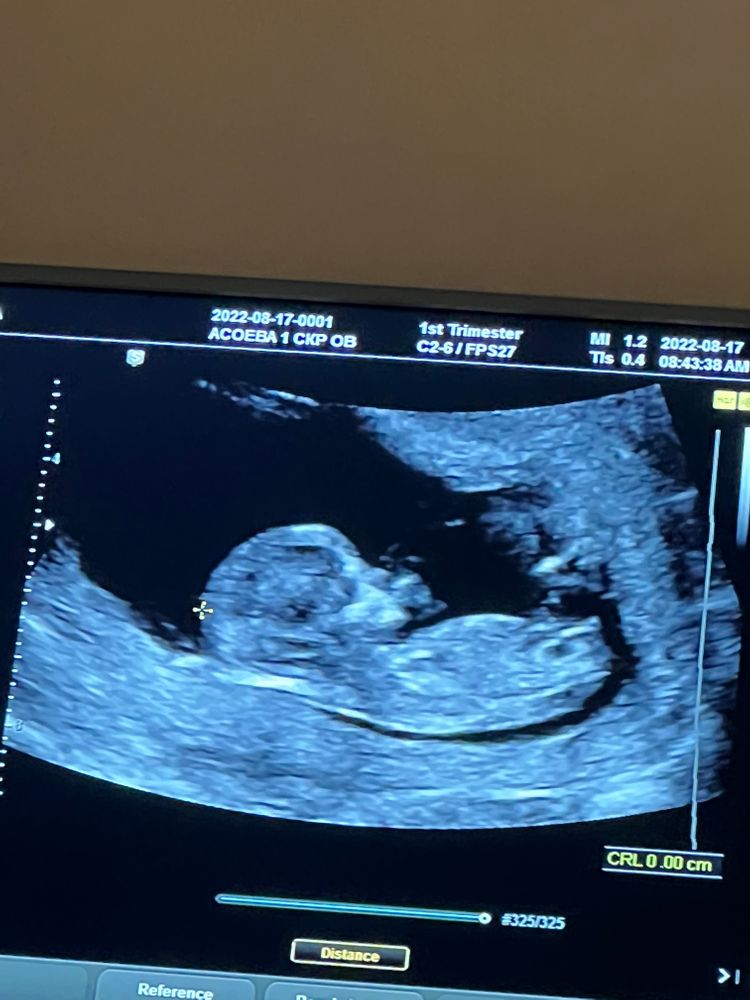

От хгч на 21 дпп 1190 до первого скрининга 😍😍